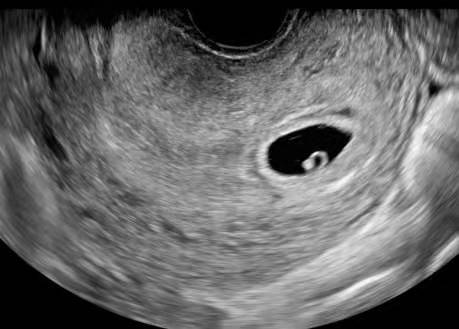

孕6周胎芽发育简报,b超单上写有这"四物",表明"坐胎"稳定_卵黄

图片尺寸300x225